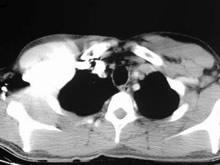

大动脉炎,是指主动脉及其主要分支及肺动脉的慢性进行性非特异性炎变,以引起不同部位的狭窄或闭塞为主,少数病人因炎症破坏动脉壁的中层,而致动脉扩张或动脉瘤,因病变的部位不同,其临床表现也不同。[1]

۞ 大动脉炎的影像学表现

۞ 大动脉炎的影像学检查